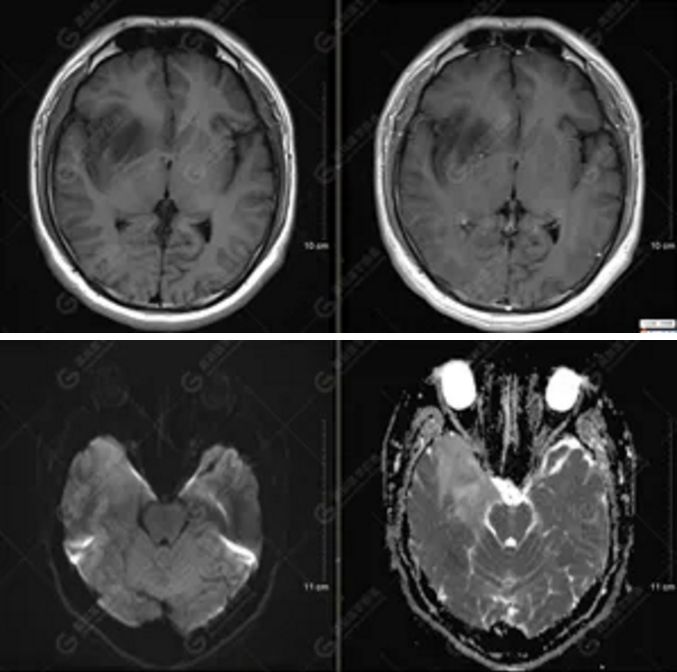

MR影像圖

【MRI平掃及增強(qiáng)檢查所見(jiàn)】右側(cè)額顳島葉、右側(cè)海馬及右側(cè)基底節(jié)區(qū)見(jiàn)一團(tuán)塊狀異常信號(hào)影,累及右側(cè)下丘腦及視交叉,大小約5.1cm×4.5cm×4.3cm,呈長(zhǎng)T1長(zhǎng)T2信號(hào),F(xiàn)LAIR序列呈等、稍高信號(hào),DWI序列呈稍高信號(hào),ADC圖高信號(hào),增強(qiáng)后無(wú)明顯強(qiáng)化;病灶周?chē)?jiàn)片狀長(zhǎng)T1長(zhǎng)T2水腫信號(hào)影,F(xiàn)LAIR序列呈高信號(hào),病灶內(nèi)見(jiàn)右側(cè)大腦中動(dòng)脈穿行。余腦實(shí)質(zhì)內(nèi)未見(jiàn)局灶性信號(hào)異常,增強(qiáng)后未見(jiàn)異常強(qiáng)化。右側(cè)側(cè)腦室輕度受壓,余腦室、腦池大小、形態(tài)均正常,中線(xiàn)結(jié)構(gòu)居中